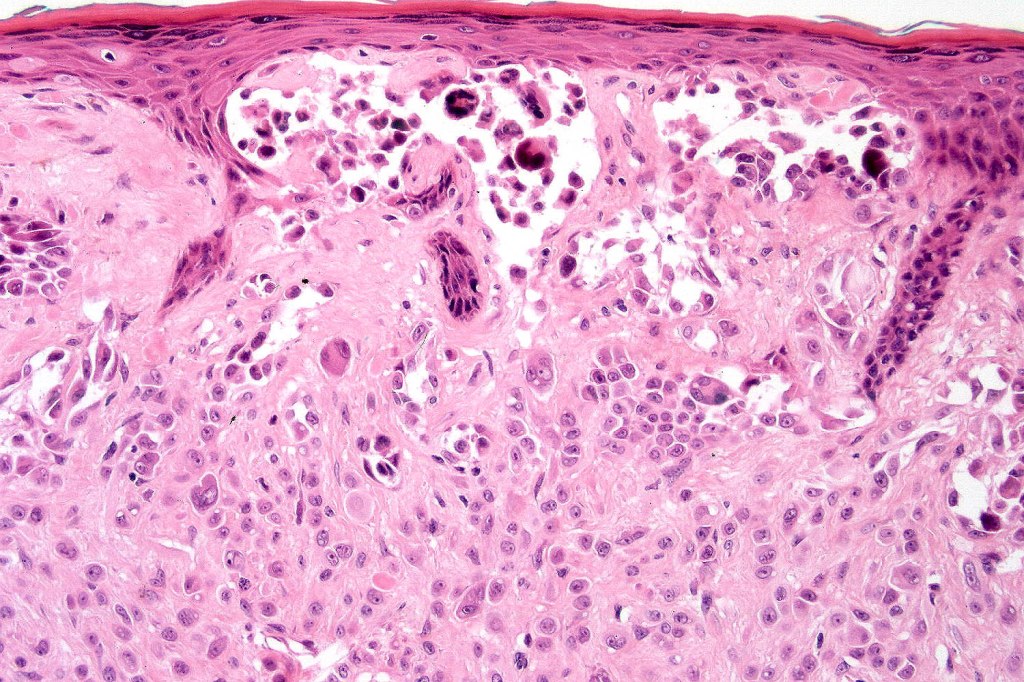

•Junctional nests often vertically orientated, dyscohesive with a surrounding retraction artifact

•Epithelioid cell variants often show greater pleomorphism and cells can frequently appear bizarre with abundant, sometimes ground glass cytoplasm and large vesicular nuclei with prominent eosinophilic nucleoli, multinucleate cells are often seen

•Intracytoplasmic pseudoinclusions commonly present in epithelioid cells

•Mitoses can brisk in younger patients and should not be taken as indicating melanoma

•Mitoses are restricted to the superficial aspect on the nevus and are never atypical

•Single cell Pgetoid spread may be seen in the center of the nevus or transpeidermal elimination of nests

•Kamino bodies (often multiple) are a characteristic feature